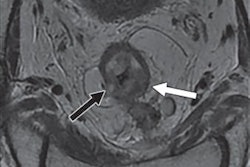

TULSA-PRO procedures begin with the insertion into the urethra of a rod-shaped device that includes 10 ultrasound-generating elements that can cover the entire prostate gland. One or more of the components then transmits sound waves to heat and destroy the targeted prostate tissue. Software automatically controls the components to adjust the shape, direction, and strength of the therapeutic ultrasound beam. The entire procedure takes place in an MRI scanner so that clinicians can closely monitor treatment and the degree and location of heating.

Through TULSA, prostate volume among the subjects decreased on average from 39 cubic cm before the treatment to 3.8 cubic cm 12 months later. In addition, clinically significant cancer was eradicated in 80% of the patients, with 72 (65%) men showing no signs of any cancer in a biopsy after one year. Overall PSA levels also decreased by a median of 95% at one-year follow-up, and there were low rates of severe toxicity and no bowel complications.

Real-time MRI thermometry and feedback control. Video courtesy of the RSNA.